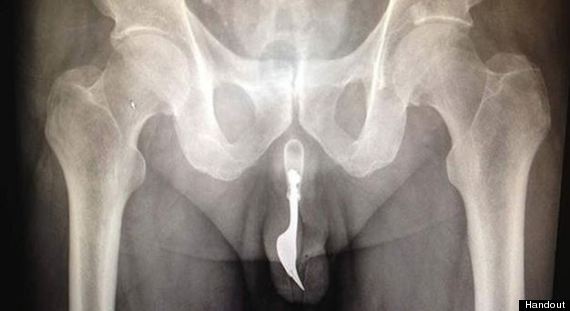

L’oggetto era una forchetta che l’uomo si era infilato nel pene sperando di riuscire ad ottenere un minimo di piacere sessuale dall’esperienza. Purtroppo per il paziente, l’ oggetto lungo 10cm si è incastrato nell’uretra costringendolo a dirigersi di corsa all’ospedale. Dopo aver valutato tutte le opzioni possibili, i chirurghi hanno rimosso l’oggetto con un forcipe e del lubrificante.